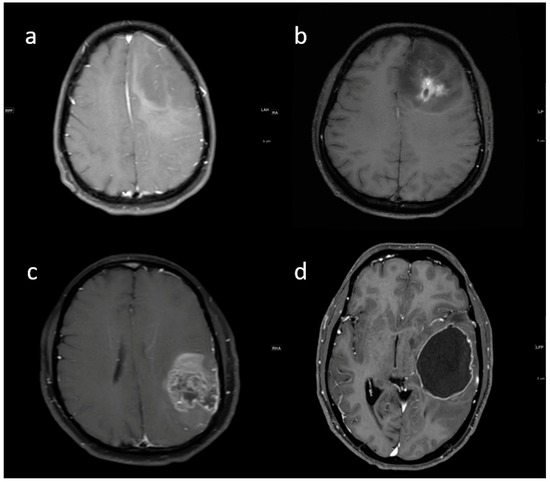

3.2. MRI Parameters of IDH-Wildtype vs. Mutant Phenotype Tumors

| Variable | Parameter | IDH-Mutated (n = 19) | IDH-Wildtype (n = 129) | p-Value |

|---|---|---|---|---|

| Enhancement I | Mild | 9 (47.4) | 5 (3.9) | <0.001 |

| Moderate | 6 (31.6) | 25 (19.4) | ||

| Severe | 4 (21.1) | 99 (76.7) | ||

| Enhancement III | Rim | 6 (31.6) | 104 (80.6) | <0.001 |

| Nodular | 0 | 2 (1.6) | ||

| Patchy | 11 (57.9) | 13 (10.1) | ||

| Solid | 2 (10.5) | 10 (7.8) | ||

| Necrosis | None | 3 (15.8) | 3 (2.3) | <0.001 |

| <25% | 11 (57.9) | 14 (10.9) | ||

| 25- 50% | 2 (10.5) | 35 (27.1) | ||

| >50% | 3 (15.8) | 77 (59.7) | ||

| Dural enhancement | AbsentPresent | 07 (70.0) | 31 (24.0)48 (52.7) | 0.013 |

| Edema | None | 3 (15.8) | 3 (2.3) | 0.025 |

| <tumor volume | 11 (57.9) | 68 (52.7) | ||

| Equal to tumor volume | 4 (21.1) | 35 (27.1) | ||

| >tumor volume | 1 (5.3) | 23 (17.8) | ||

| Cysts * | No | 11 (57.9) | 115 (89.1) | 0.001 |

| Yes | 6 (31.6) | 14 (10.9) | ||

| Subcortical involvement | Involved | 18 (94.7) | 94 (72.9) | 0.044 |

| Not involved | 1 (5.3) | 35 (27.1) | ||

| rCBV | Median (IQR) | 1.8 [1.4–2.0] | 2.6 [1.9–3.5] | 0.001 |